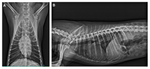

Las imágenes radiológicas sirvieron para evaluar la extensión local y regional de la enfermedad, ayudando a identificar evidencias de metástasis. La radiografía torácica (ver figura 1A) permitió evaluar la integridad de los pulmones, no mostró evidencia de nódulos pulmonares múltiples, adenomegalia mediastínica o derrame pleural, que forman el patrón metastásico. De manera similar, la radiografía abdominal (ver figura 1B) permitió asegurar que no existía metástasis hepáticas/esplénicas o invasión local, al mostrar al espécimen canino sin hepatomegalia y esplenomegalia, presencia de masas abdominales o calcificaciones. La toma de imágenes radiográficas de la región mamaria no se consideró necesaria debido a las limitaciones de la técnica para distinguir la naturaleza y condición de las lesiones neoplásicas.

Figura 1. Imágenes radiológicas de un canino hembra Husky Siberiano de 10 años de edad. (A) Radiografía torácica con proyección ventrodorsal, (B) Radiografía abdominal con proyección lateral.